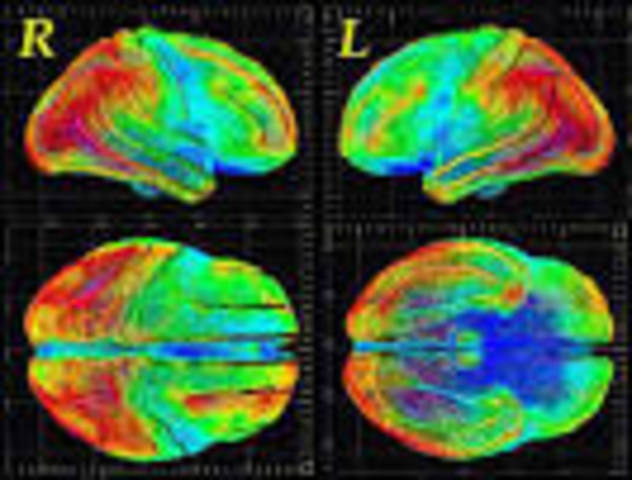

MRI was introduced clinically, and during the 1980s a veritable explosion of technical refinements and diagnostic MR applications took place. Scientists soon learned that the large blood flow changes measured by PET could also be imaged by the correct type of MRI. Functional magnetic resonance imaging (fMRI) was born, and since the 1990s, fMRI has come to dominate the brain mapping field due to its low invasiveness, lack of radiation exposure, and relatively wide availability.

• Neuroimaging

Neuroimaging

The field of neuroimaging reached the stage where limited practical applications of functional brain imaging have become feasible. The main application area is crude forms of brain-computer interface.